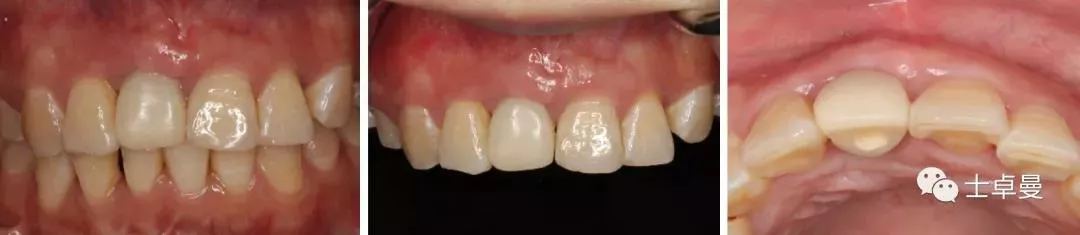

二期术前口内照及CBCT

种植体植入后6个月

·      安装临时修复体;

·      临时修复体安装2个月后调整穿龈形态及邻面接触点位置;

·      临时修复体安装6个月后,牙龈形态良好,唇侧软组织稳定;

·      个性化取模;

·      最终修复;

·      最终修复CBCT。

本病例利用颏部的自体骨块修复前牙区垂直骨缺损,以确保能在理想的位点进行种植体的植入,从而获得良好的美学及功能效果。